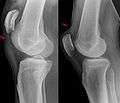

Quadriceps tendon rupture in plain X-ray

Quadriceps tendon rupture in plain X-ray: Incomplete rupture with haematoma in tendon.

X-ray of a tear of the patellar tendon. On the left: The kneecap is pulled up. On the right: Significant dent in the soft tissue above the kneecap.